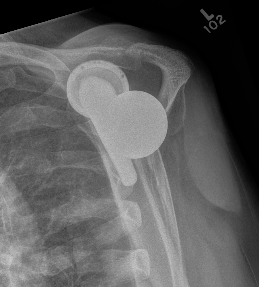

Loosening

Failed Glenoid Reverse TSRReverse TSR Loose Metaglene

Loose metaglene

Lysis around humeral and glenoid component

Reverse TSR Loose Glenosphere from Metaglene

Glenosphere loosening from metaglene